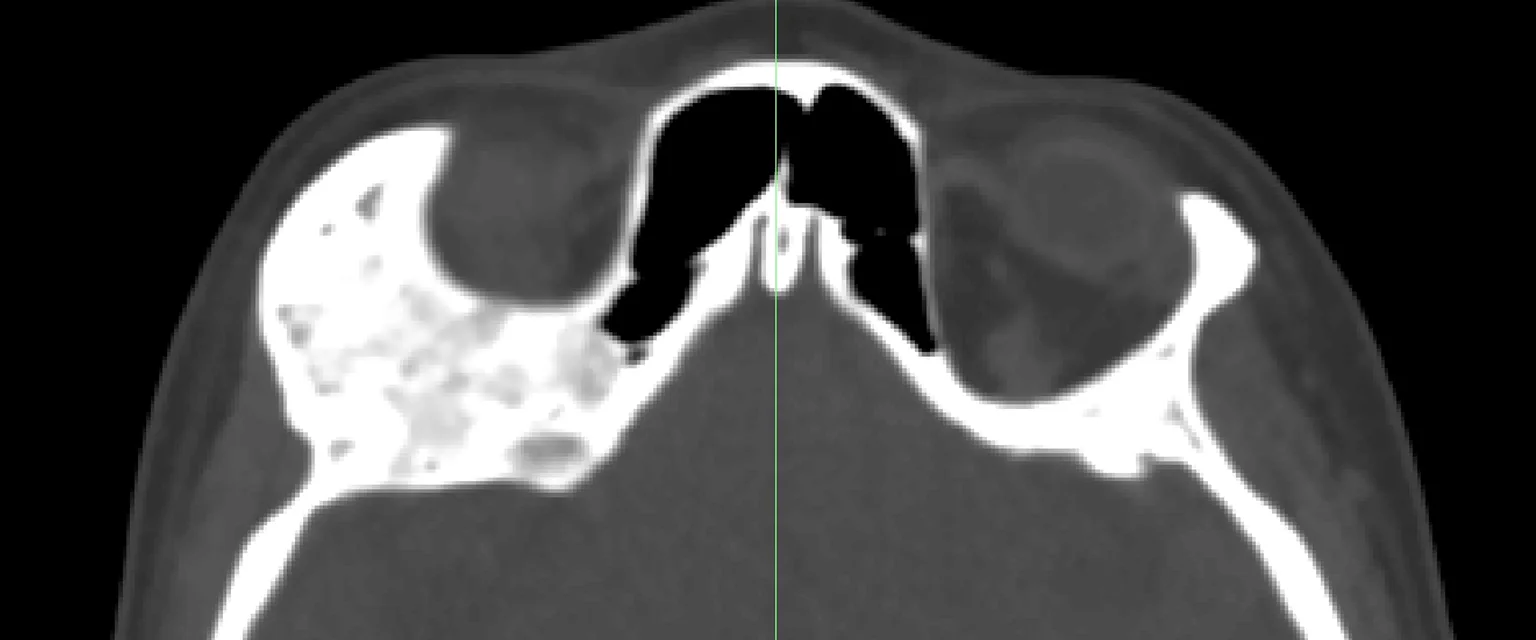

Clinical Background

By collaborating closely with a maxillofacial surgeon, I improved the speed, predictability and accuracy of this critical, complex procedure.  The patient had a bone tumour which was invading the orbit, applying pressure to the optic nerve and threatening their eyesight.